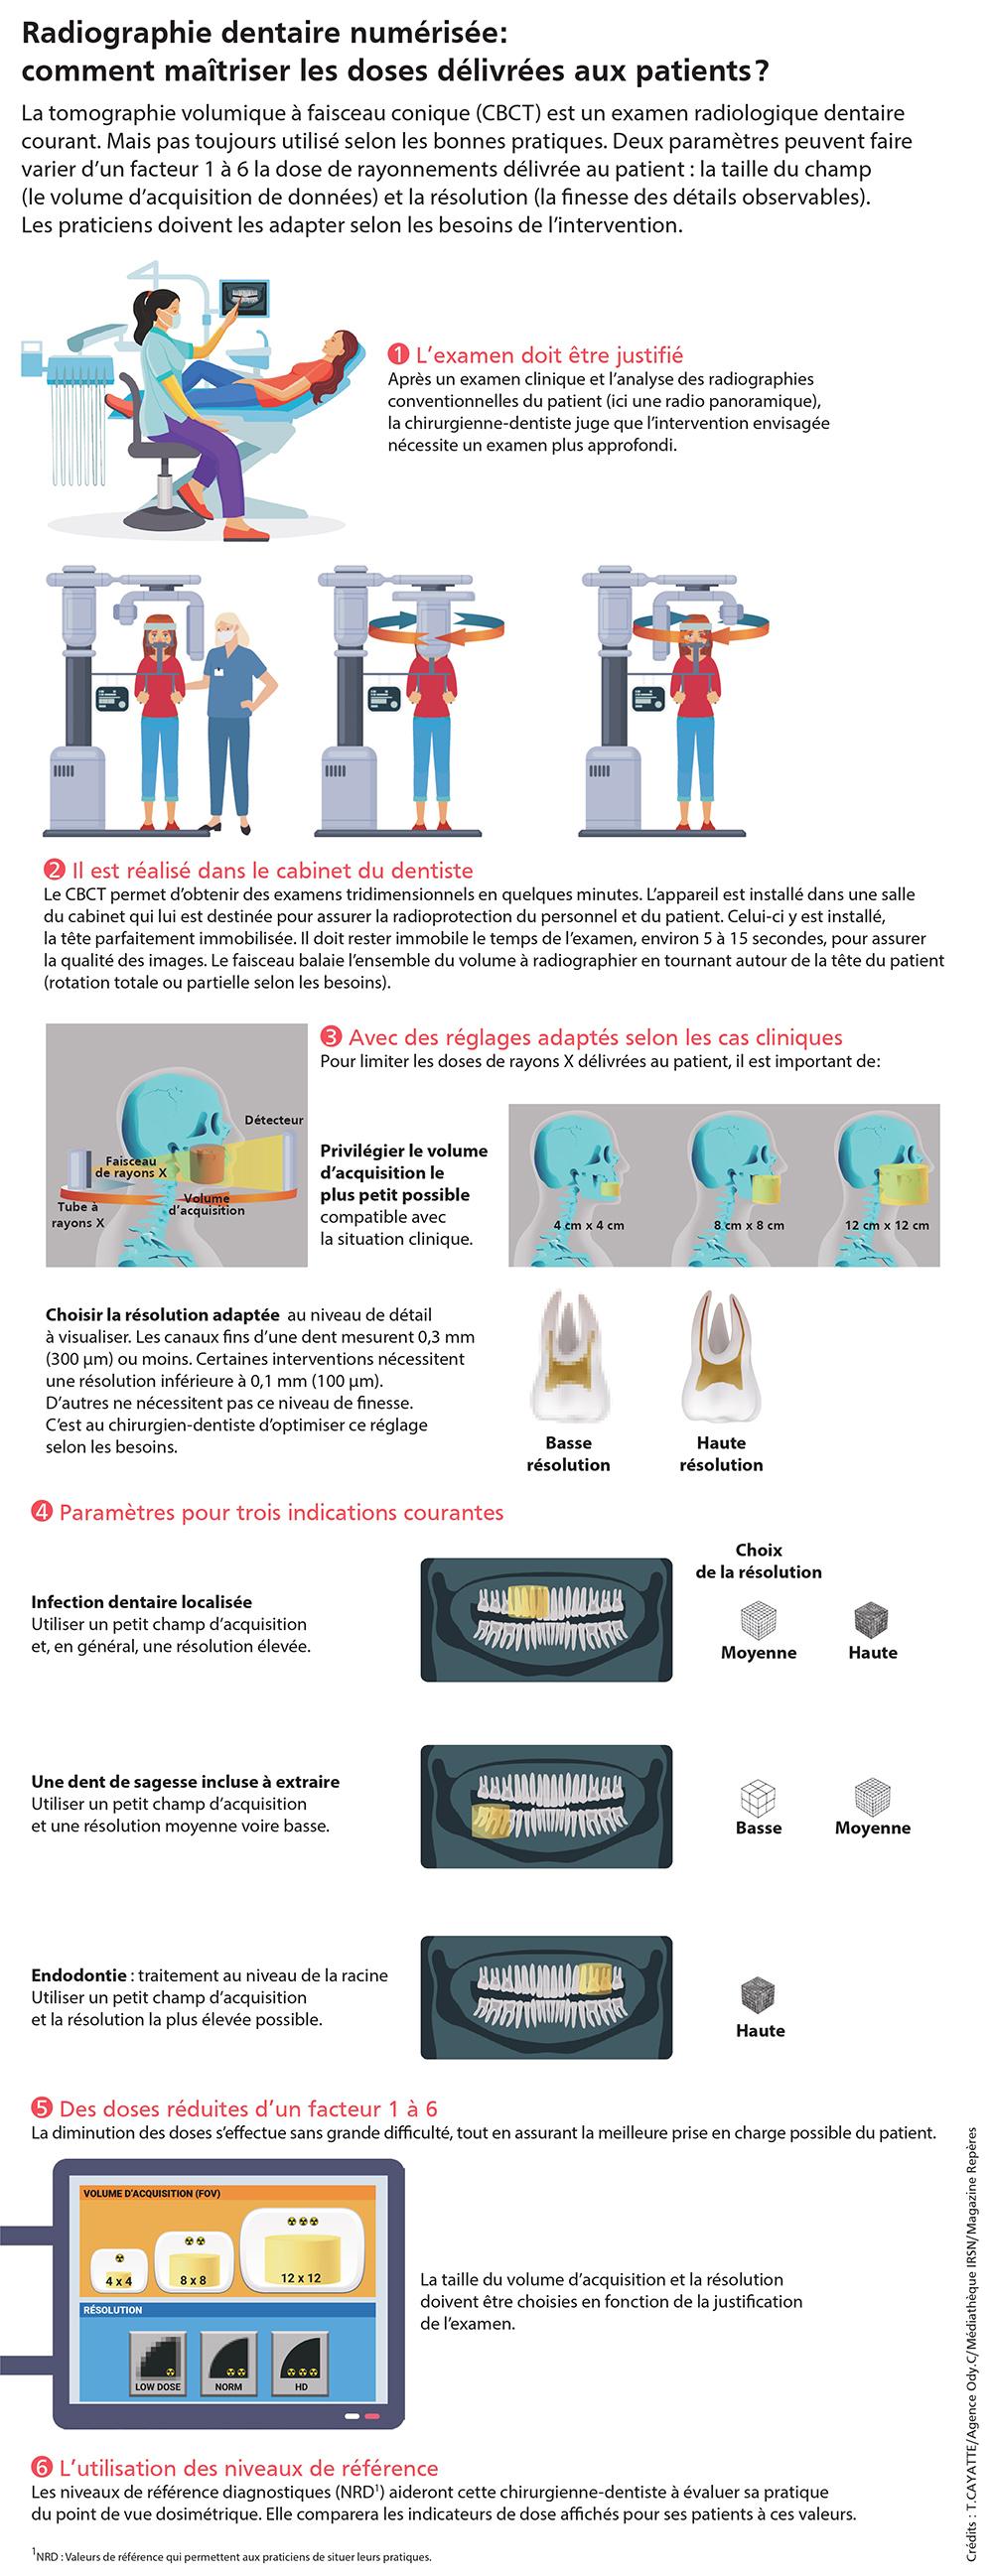

INFOGRAPHIE – Radiographie dentaire numérisée : comment maîtriser les doses délivrées aux patients ?

La tomographie volumique à faisceau conique (CBCT) est un examen radiologique dentaire courant. Mais pas toujours utilisé selon les bonnes pratiques. Deux paramètres peuvent faire varier d’un facteur 1 à 6 la dose de rayonnements délivrée au patient : la taille du champ (le volume d’acquisition de données) et la résolution (la finesse des détails observables). Les praticiens doivent les adapter selon les besoins de l’intervention.

"L’intérêt croissant, depuis une dizaine d’années, des chirurgiens-dentistes pour la tomographie volumique à faisceau conique est lié à la qualité des images obtenues avec ces équipements radiologiques de pointe installés dans leur cabinet. Celles-ci sont en trois dimensions, comme les scanners réalisés en centre radiologique, mais de meilleure résolution (jusqu’à moins de 0,1 mm). Toujours comparées à celles des scanners, elles sont obtenues avec un niveau plus bas de dose de rayons X délivrés aux patients, même si celui-ci est parfois bien plus élevé que pour les panoramiques dentaires et les radios intrabuccales classiques.

À la différence des équipements radiologiques habituels, dont les possibilités de réglage sont très limitées, la tomographie volumique à faisceau conique nécessite une certaine maîtrise. Deux principaux réglages sont à réaliser, dont dépendent les doses délivrées au patient : la taille du champ d’acquisition des données – en fonction du volume à explorer et de la résolution – selon la finesse des détails recherchés."

"À la demande de l’Autorité de sûreté nucléaire, nous avons mené une enquête nationale auprès des cabinets dentaires et centres d’imagerie médicale pour proposer les premiers niveaux de référence diagnostiques (NRD) pour les examens de CBCT dentaire. Les professionnels de santé concernés pourront comparer les doses délivrées aux patients à ces valeurs de référence dans une optique d’optimisation des expositions. La collecte de données a été faite sur la base du volontariat. Nous avons pu exploiter les retours d’environ 150 établissements (à 90 % des cabinets dentaires), ce qui est peu par rapport aux 2 700 appareils installés en France, mais suffisant pour faire une analyse statistique. Compte tenu des données reçues, nous proposons des NRD pour trois indications chez l’adulte : l’implantologie, les dents incluses et l’endodontie. Cette enquête a révélé que les chirurgiens-dentistes ne maîtrisent pas toujours les fonctionnalités de leurs appareils, dont les notices et les affichages sont parfois peu clairs. Lors de la mise en place des NRD, un accompagnement des professionnels sera nécessaire, avec des formations proposées par des associations professionnelles ou encore par l’amélioration des notices à la charge des constructeurs."